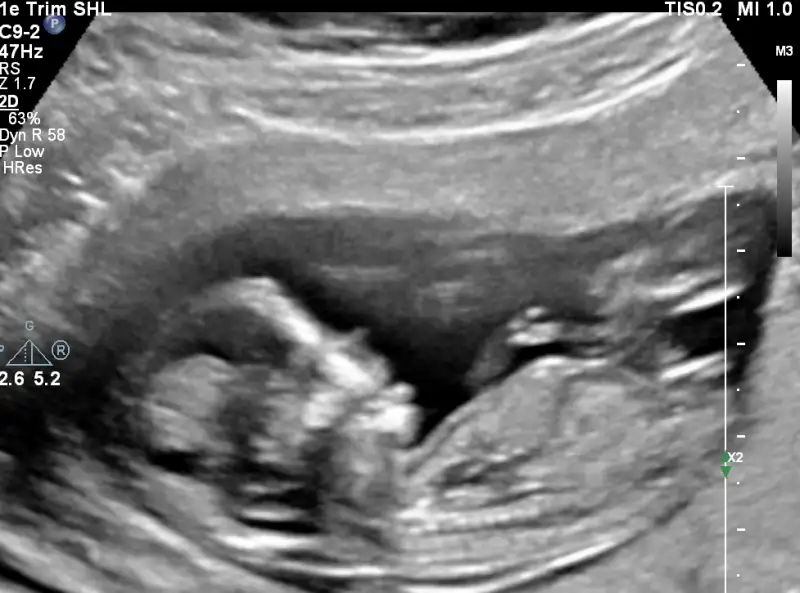

Benimki ultrasonda oyle gorunuyordu cunku kendi cevresi seklinde yuvarlaniyordu zipliyordu. cok komik ya.

Benim ilk hamileligimde kizdi. Ve devamli ayaklariyla tepiniyordu kosuyormus gibi. Ama bu hamileligimde farkli zipliyor kendi cevresinde donuyor falan bilmiyorum artik kiz mi erkek mi bu seferki